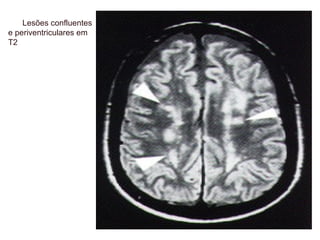

Doença de Pequenos Vasos

Déficit em lobo frontal

Função executiva alterada

Prejuízo atencional

Sintomas depressivos

Marcha alterada

Parkinsonismo

Prejuízo futuante de memória

Curso subclínico

Lesões confluentes

e periventriculares em

T2